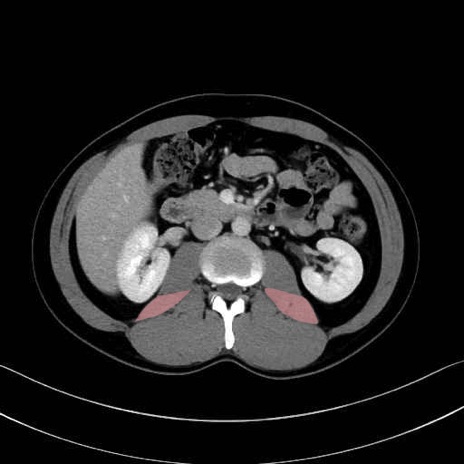

大腰筋 (Psoas major)